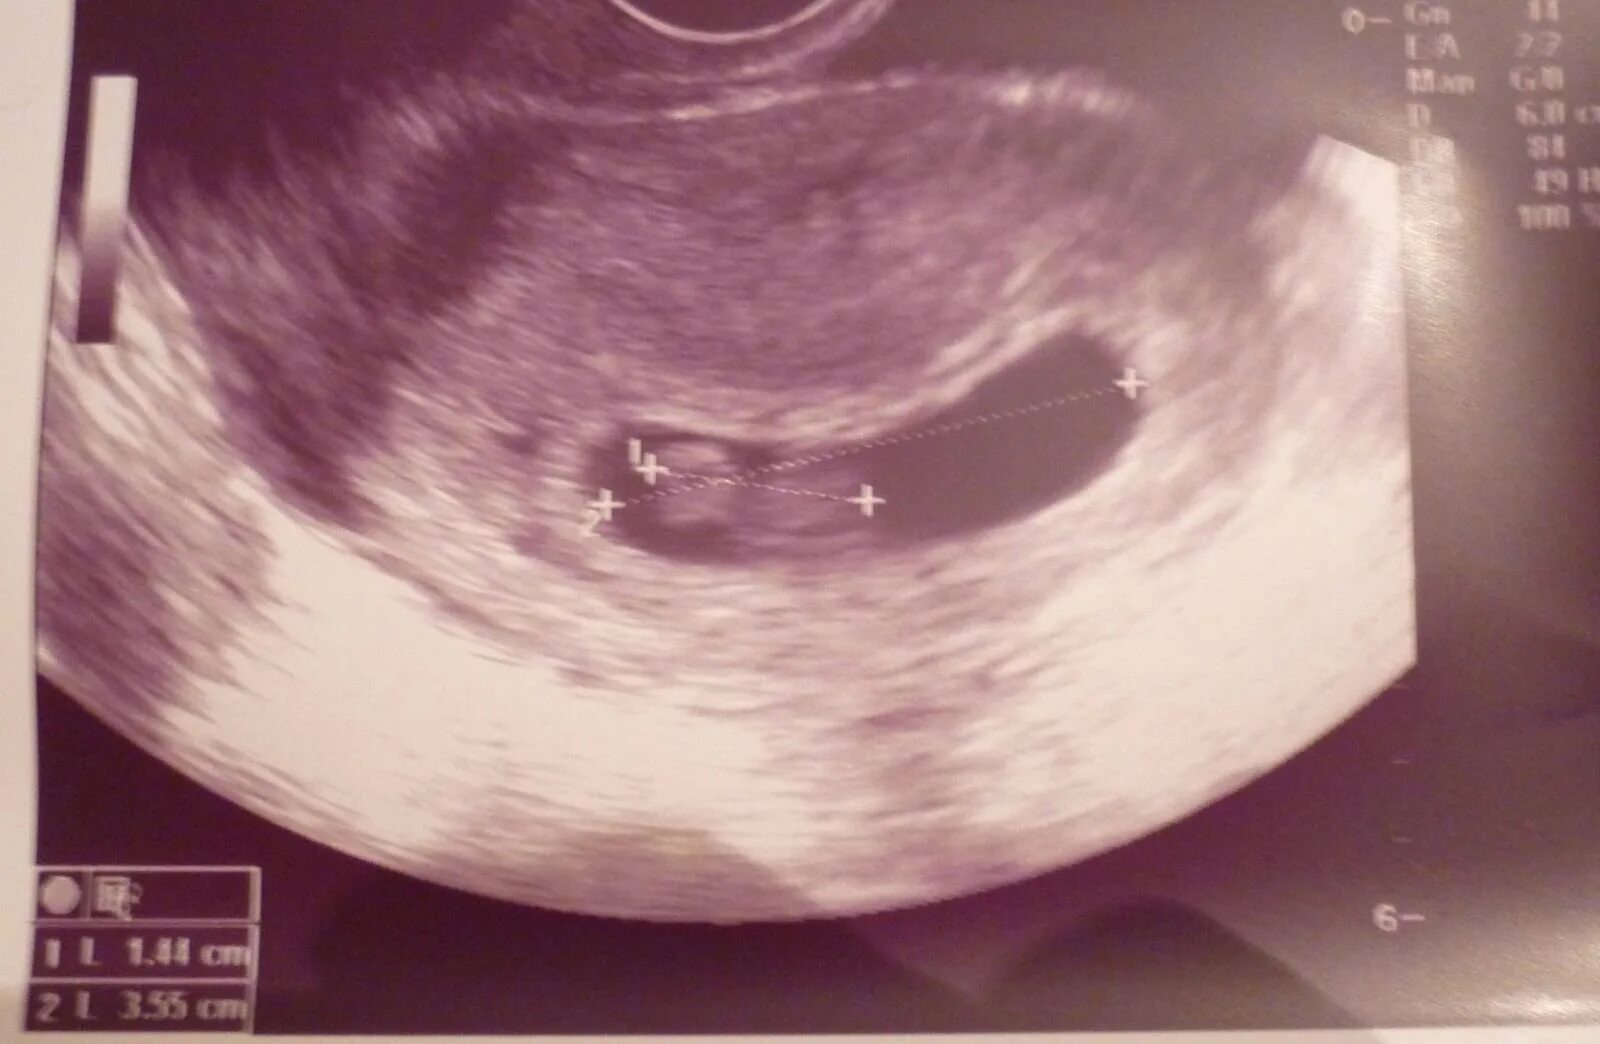

3 недели 6